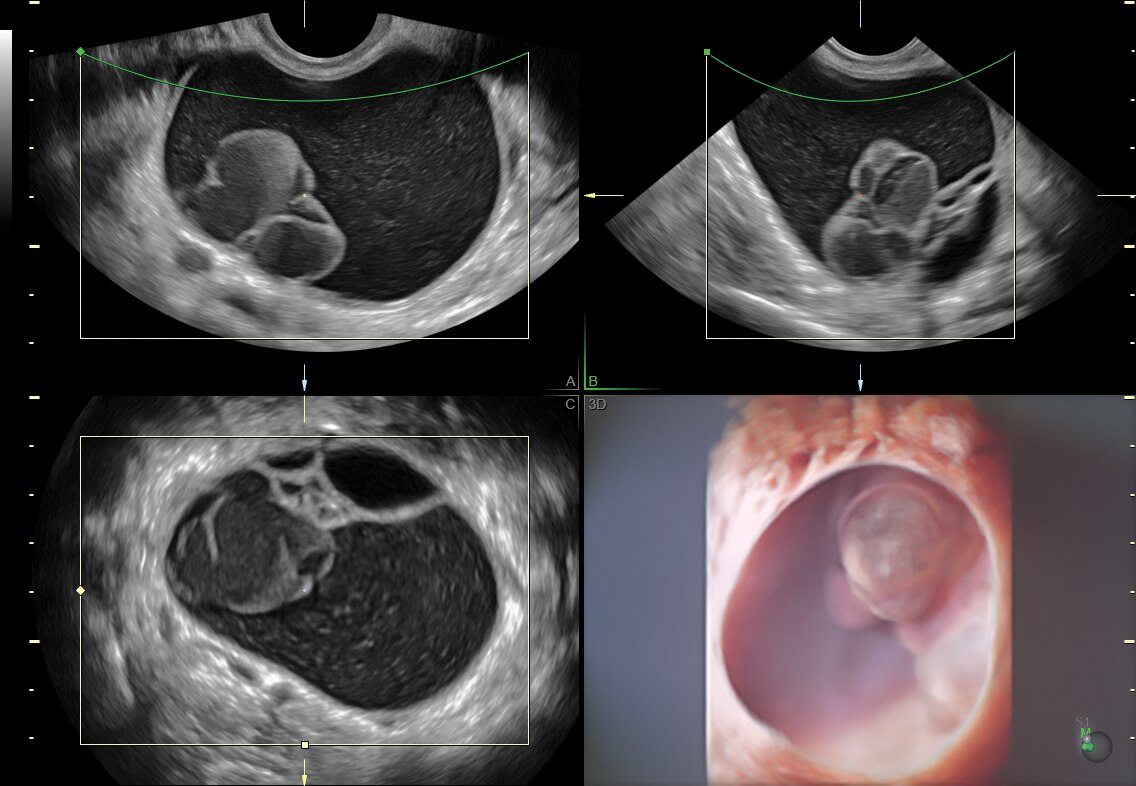

fetalHQ

fetalHQ — Realize uma avaliação fácil, rápida e abrangente do tamanho, forma e contratilidade do coração fetal a partir da visualização de 4 câmaras usando medidas baseadas em imagens 2D e rastreamento de nódoa. O fetalHQ contém uma página de relatório detalhada, incluindo índices z e percentis para cada uma das medidas cardíacas.